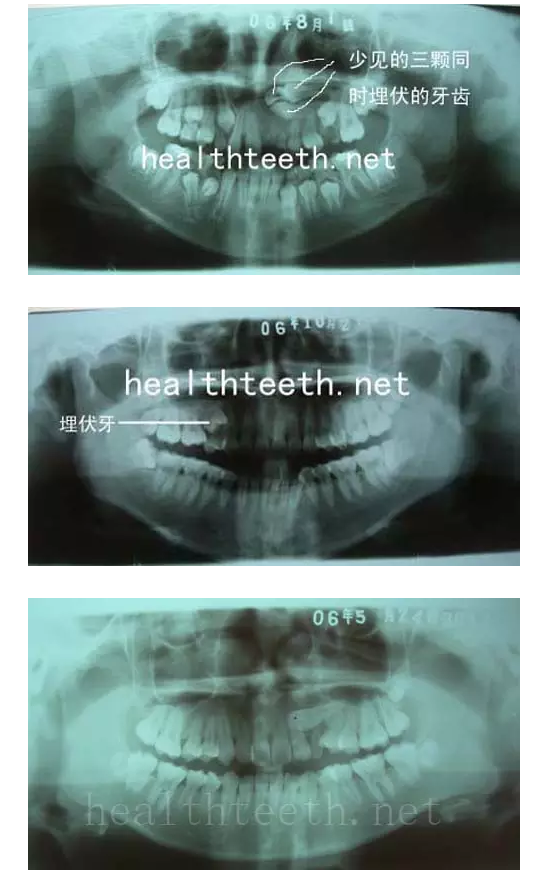

2、埋伏牙

其他埋伏牙

3、多生牙

病例1

病例2

病例3,同時多生兩顆牙齒